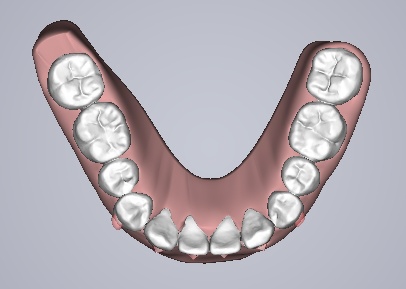

该技术可根据求美者的颌面形态开展个性化设计,通过计算机三维图像技术模拟牙齿移动后生产的每一副矫治器,在戴入后牙齿就会有受力感觉,并向矫治器设计的位置移动,通常每两周更换一副矫治器,牙齿就会从初始的畸形状态逐渐移动至正常排列状态,矫治时间长短取决于患者牙颌畸形的严重程度,一般需要半年到一年时间就能解决牙齿不齐等问题,该技术成为国内外爱美人士矫正牙齿的不二选择。

治疗方案动画

治疗预计效果和实际效果